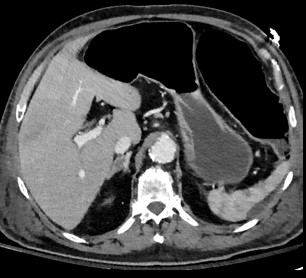

Foie

Voie biliaire

Pancreas